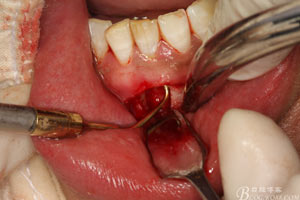

圖7.局部麻醉下,行下前牙唇側(cè)弧形切口,翻瓣可見31唇側(cè)骨壁有缺損,并有根充物暴露